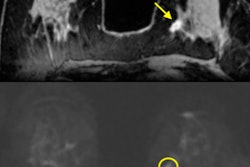

The approach features a form of diffusion-weighted MRI (DWI-MRI) known as diffusion kurtosis imaging, which analyzes the distribution of water to evaluate breast tissue structures at a microscopic level. A software algorithm based on a kurtosis radiomics model then extracts imaging data to accurately characterize the lesions (Radiology, February 20, 2018).

"[The] model ... reduces false-positive results by 70% in lesions classified as BI-RADS 4 or 5 at screening mammography while retaining sensitivity greater than 98%," wrote lead author Dr. Sebastian Bickelhaupt, from the German Cancer Research Center in Heidelberg, and colleagues. "Since malignant lesions disrupt the tissue structures at this level, diffusion kurtosis might serve as a relevant marker of changes."

"A radiomics breast cancer model based on DWI with adapted kurtosis fitting allowed for improved differentiation between malignant and benign breast lesions in both training and independent test datasets acquired by using MR imaging machines from different vendors at different institutions," Bickelhaupt and colleagues wrote.